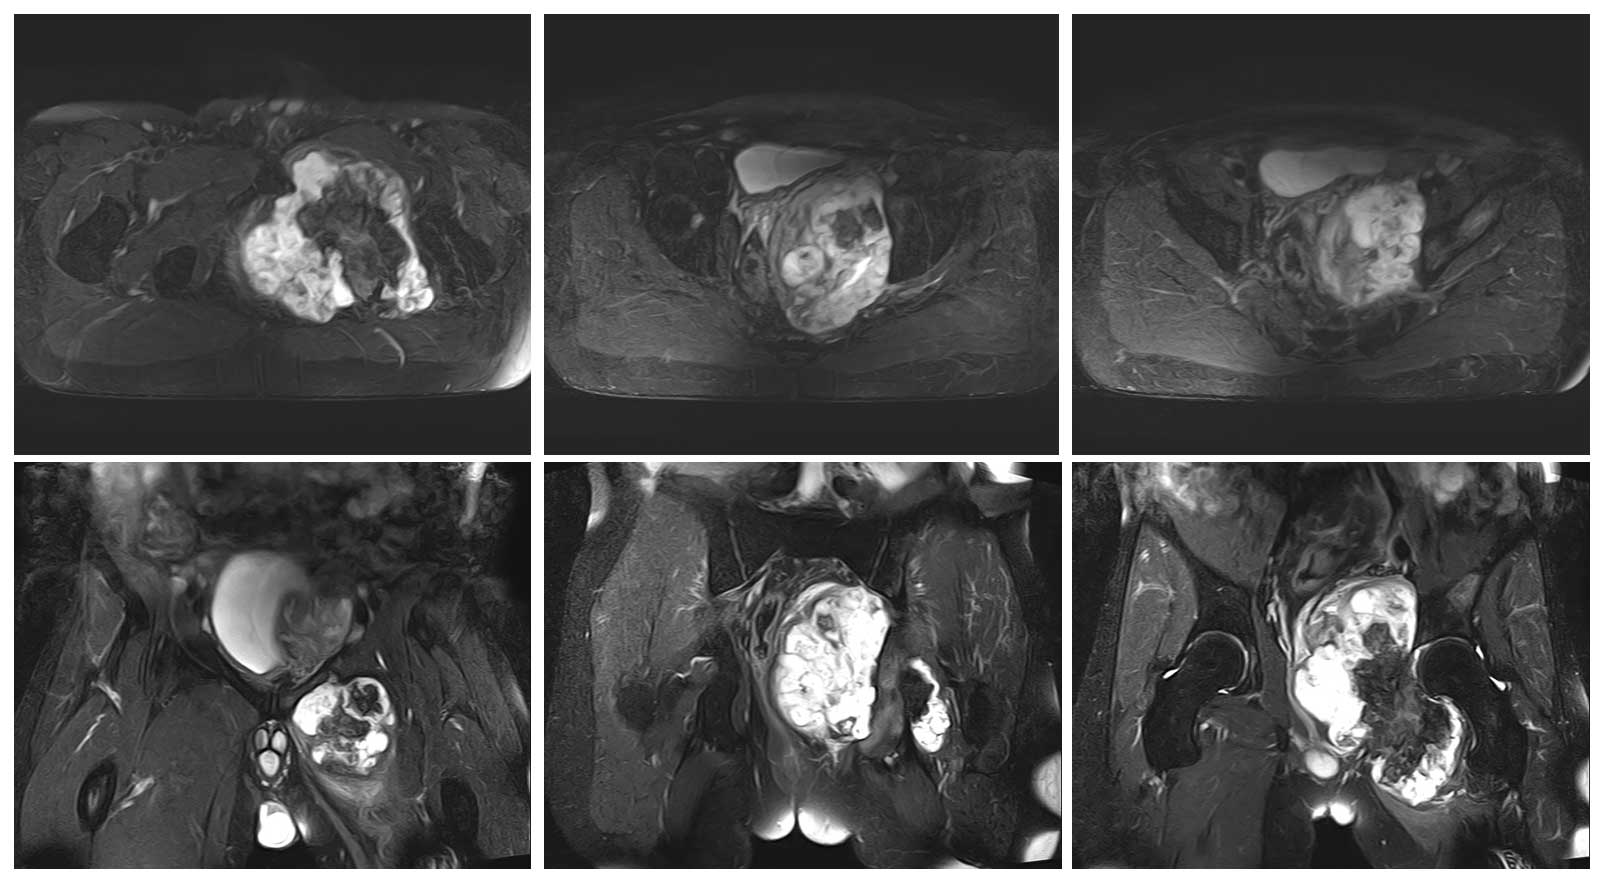

Ameliyat Öncesi: MR’da aynı lokalizasyonda heterojen büyük yumuşak doku komponentinin eşlik ettiği tümör dokusu görülmekte.